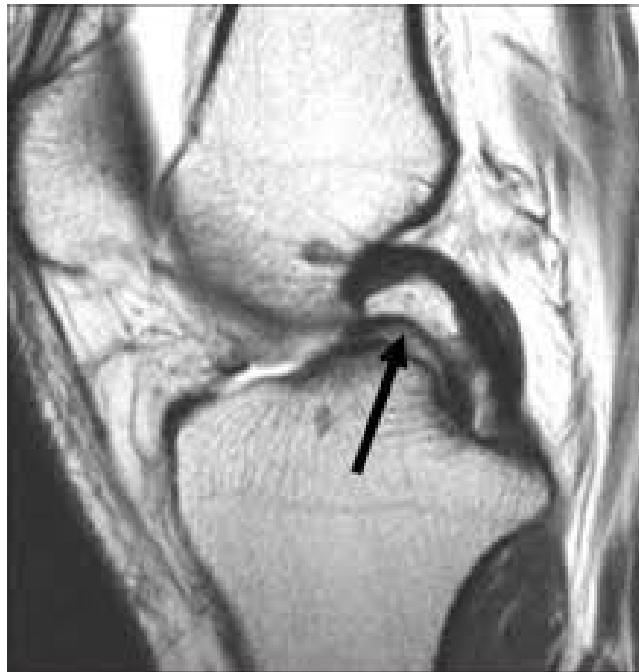

Imaging

Question: What is your finding?

Additional Case Questions

Questions for discussion:

- What is the diagnosis?

- What is the sign called? pocket handle

- What is the treatment?